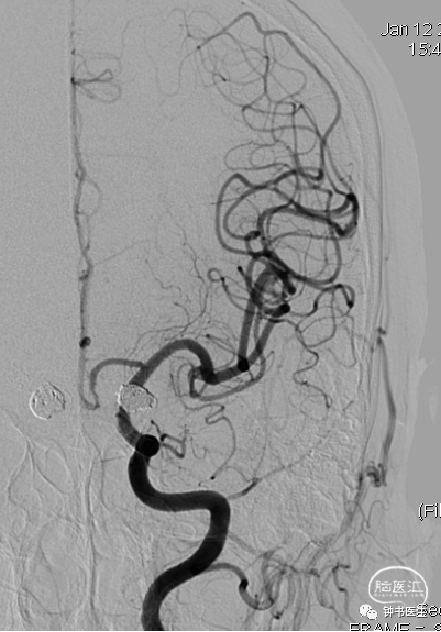

术后

术后6个月DSA复查:动脉瘤无残留、复发,治愈!

术后13个月DSA复查:动脉瘤无残留、复发,治愈!